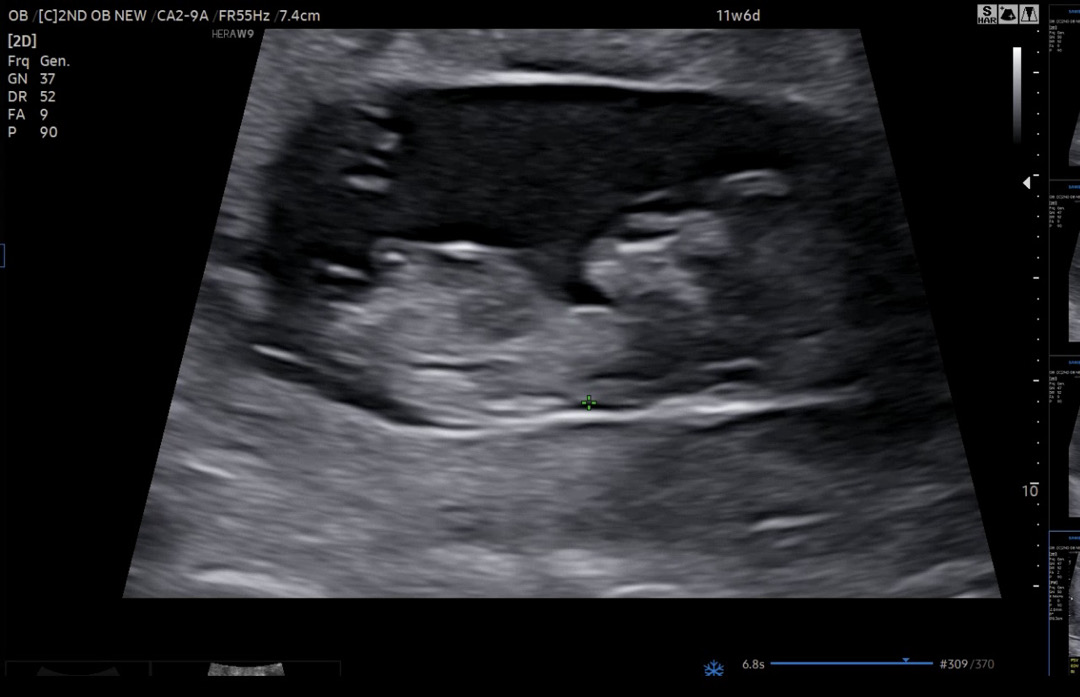

11주 6일에 1차 기형아 검사를 하고 왔는데 성별이 너무 궁금하네요. 아직 이건 예측할 수 없겠죠? 딸 일지 아들 일지 너무 너무 궁금합니다.

지금 첫째가 아들이여서 둘째는 딸 원하고 있습니다.☺️